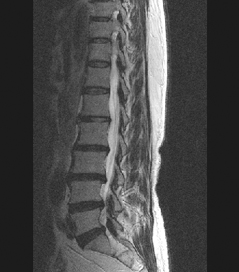

64세 여자환자는 2개월 전부터 요통과 다리 바깥쪽과 발등, 종아리 뒤쪽으로 저린 감각이 심해져서 개인병원에 들러 평가 및 물리치료를 받았으나 별다른 호전이 없고, 1주일 전부터는 허리를 숙이거나 물건을 들 때, 오래 걸을 때 통증이 더 심해져서 본원을 방문하였다. 12년전 집안일을 심하게 하고 난 후부터 간헐적인 요통을 발생하였으며, 별다른 치료 없이 지냈으며, 4년전 무거운 물건 들고 난 후 심하게 요통과 둔부의 통증까지 발생하여 MRI 촬영상 L1-2, L3-4-5, L5-S1 HNP와 Lt. L4 & both L5 nerve compression, Lt. S1 nerve compression 진단받고 Epidural steroid injection을 받고 통증 경감되었고, 간헐적으로 통증이 발생하였으나 별다른 치료 없이 헬스클럽에서 지속적인 운동으로 관리하였다.

• 척추 방사선 사진2